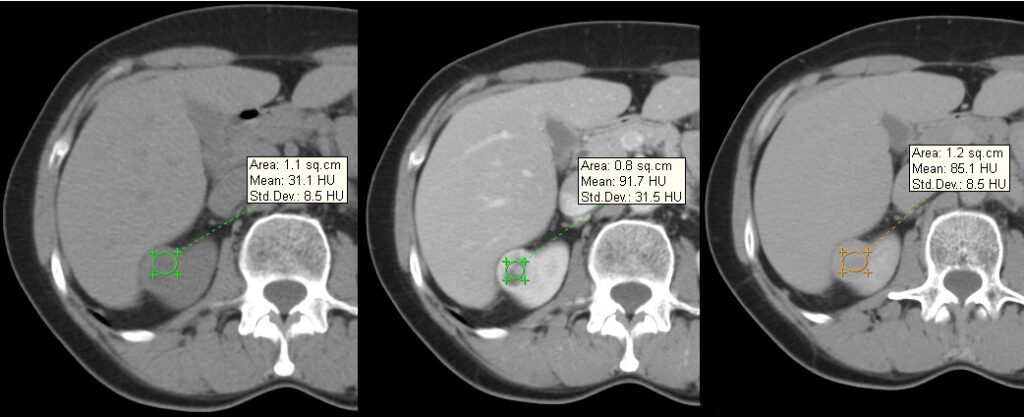

Representa el subtipo más común (70%), se origina a partir de la corteza renal y tiene un componente expansivo. Este tumor tiene un alto contenido de lípidos con áreas de necrosis y focos hemorrágicos, por lo que su característica principal es la heterogeneidad (9); gracias a su amplia red de capilares y vasculatura, con el medio de contraste el realce es evidente en la fase corticomedular de 149 +/- 46 UH, y en la fase excretora con 95 +/- 17 UH aproximadamente 8.

Una vez detectado el tumor se debe proceder a ubicar la extensión del mismo, correlacionándose en un 45% con extensión a la vena renal y metástasis a pulmón, hígado y hueso (2). La tasa de supervivencia a 5 años es del 50% 10 (Fig. 10, Fig. 11).

Se presenta como una lesión más homogénea, hipovascular, con realce tenue de hasta 91 +/- 12 UH en la fase corticomedular y 71 +/- 10 UH en la fase excretora; en los tumores de mayor tamaño pueden observarse aéreas de necrosis y hemorrágicas por lo que será más heterogéneo 8-9-10.

La tasa de supervivencia a 5 años es del 80 a 90%, por lo que se considera menos agresivo y de crecimiento lento en comparación con el de células claras 10 (Fig. 12, Fig. 13).